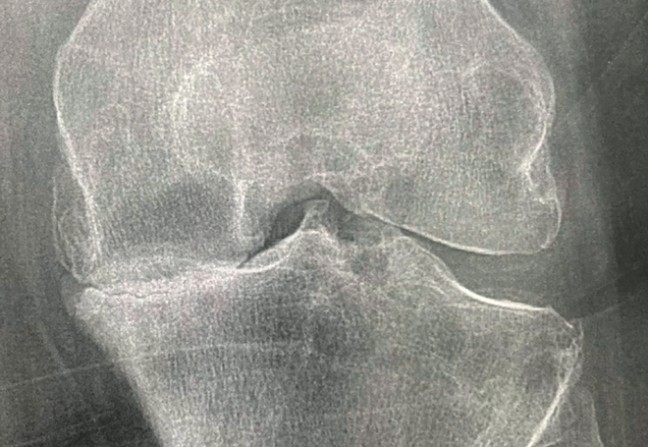

Le diagnostic se fait par l'imagerie standard, avec quatre signes cardinaux (mais qui ne sont pas forcément tous présents) :

- pincement localisé de l'interligne articulaire ;

- ostéophytes marginales ;

- ostéosclérose condensante de l'os sous-chondral ;

- géodes d'hyperpression.

Il n'y a pas de concordance radioclinique dans l'arthrose.